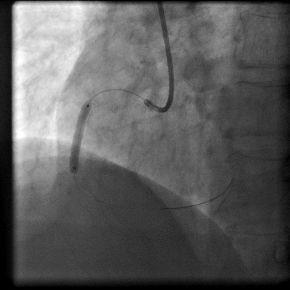

病例介绍:陈姓35岁青年男性,因“突发胸痛2小时”与凌晨1:00入我院急诊科,入院后即刻心电图提示急性下壁、后壁心肌梗死,认为应立即行急诊PCI术。立即给予足量阿斯匹林和波立维,启动急性心肌梗死救治绿色通道。导管室护士、技师、心内科医生在导管室等待,并且做好术前准备。在得到患者家属同意后,我们迅速带患者入导管室。急诊冠脉造影示:右冠状动脉近段完全闭塞,通过血栓抽吸,球囊扩张,开通闭塞血管,右冠近段成功植入药物涂层支架一枚,患者转危为安,整个过程用时28分钟。